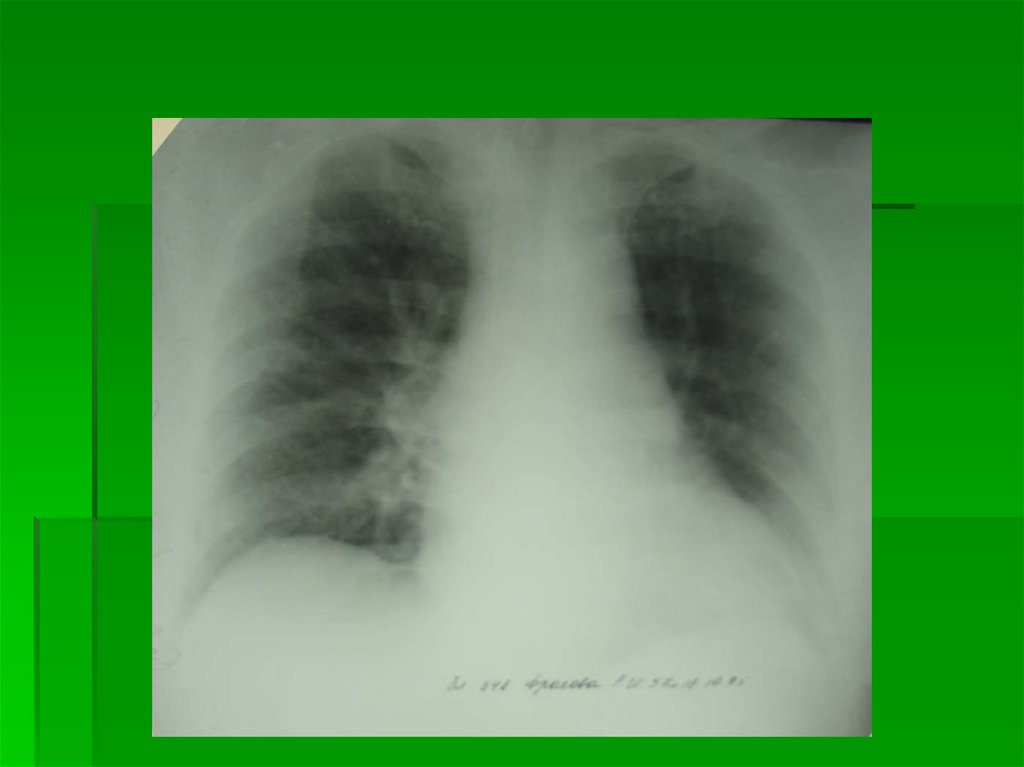

3 степень

Интерстициальный отек

легких

Выход жидкой части крови за пределы

сосудистого русла в интерстициальную

легочную ткань

Корни легких неструктурны,

гомогенизированы, однородны

На фоне корней легких – сосуды в

ортопроекции практически не

дифференцируются

Дифференцируются в ортопроекции

просветы бронхов с утолщенными стенками

в виде маленькой кольцевидной тени с

нечеткими наружными контурами

Прозрачность легких снижена за счет

обилия элементов легочного рисунка

Легочный рисунок утратил обычную

архитектонику, представлен множеством

очаговоподобных теней (расширенные

сосуды в ортопроекции)

и полигональных теней (отечные

междольковые и межальвеолярные

перегородки в ортогональной и косой

проекциях)

Лимфостаз в виде Линий Керли (Kerley) как

обязательный признак ЛВГ 3

Определяются в латерально-базальных

отделах легких (над синусом) в виде коротких

перегородочных линий L=0,5-2,5 см, широким

основанием прилежащих к грудной стенке

Нежная «волосяная» тень междолевой

плевры (лимфостаз по ходу плевры)